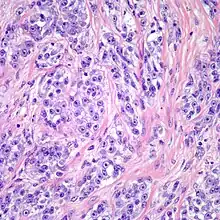

Clear cell sarcoma. Tumor cells with prominent nucleoli and clear cytoplasm are arranged in well-defined nests surrounded by dense fibrous stroma.

Despite the name clear cell sarcoma, the tumor cells do not necessarily need to have clear cytoplasm. The lesion has a distinctly nested growth pattern with a mixture of spindle, epithelioid and tumor giant cells. Approximately two thirds of the tumors contain melanin pigment. Clear cell sarcoma, similar to melanoma, has consistent positivity for S-100, HMB-45, and MITF.[6]